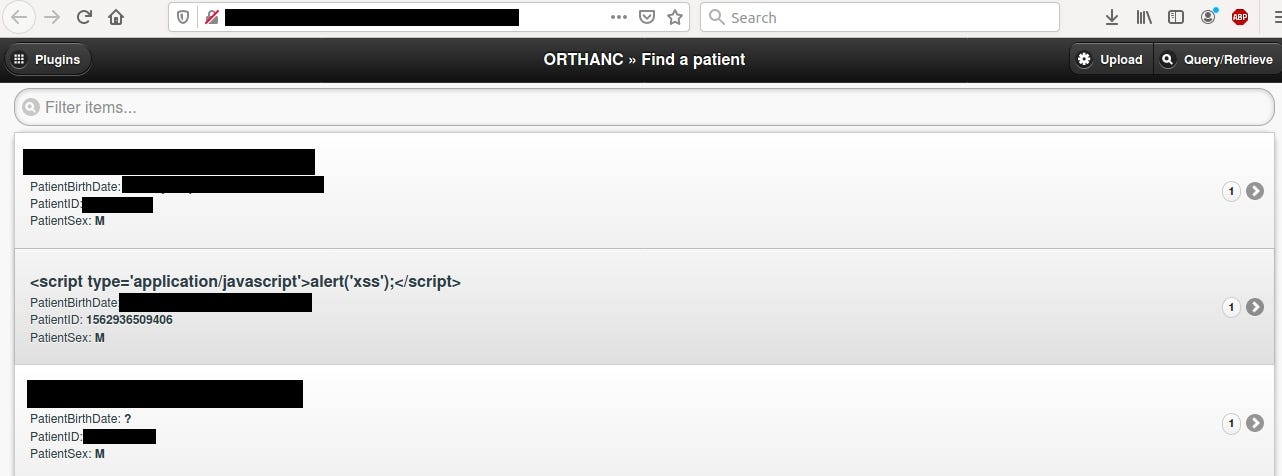

Orthanc Explorer

It’s yet another DICOM viewer software. It allows to check patient’s X-Ray scans and other medical info. A lot of Orthanc instances are open without any authentication.

It’s all fun and games until some script kiddies start to test it without proper authorization.

If you want to test functionality and GUI of this software, you can check out demo that’s publicly accessible.

https://demo.orthanc-server.com/app/explorer.html

Don’t test device/software you don’t own